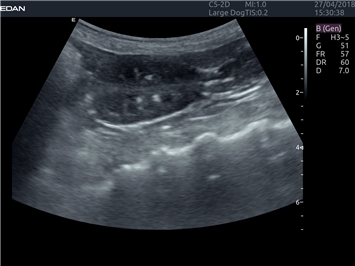

EDAN Acclarix LX4 VET

EDAN Acclarix LX4 VET представляет собой профессиональную ультразвуковую систему, специально разработанную для ветеринарных исследований. Сочетание стабильности, высокой производительности и эффективности делает эту систему идеальным выбором для современной ветеринарной практики.

• Универсальные датчики для различных видов животных

• Специализированные предустановки для ветеринарных исследований

• Гибкие протоколы исследований

Система оптимально подходит для:

• Ветеринарных клиник

• Специализированных ветеринарных центров

• Животноводческих комплексов

• Конных клиник

• Научно-исследовательских ветеринарных учреждений